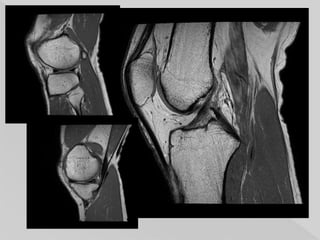

 that nuclearmagnetic resonance of protons (hydrogen ions) forms the major basis of MRI.  an intermediate sequence sharing some features of both T1 and T2.  PD offers excellent signal distinction between fluid, hyaline cartilage and fibrocartilage, which makes this sequence ideal in the assessment of joints.

• 50.

The dominant signalintensities of different tissues are: fluid (e.g. joint fluid, CSF): high signal intensity (white) muscle: intermediate signal intensity (grey) fat: high signal intensity (white) hyaline cartilage: intermediate signal intensity (grey) fibrocartilage: low signal intensity (black)